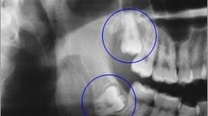

8、智齿

智齿就像是口腔中不受欢迎的“住客”。通常,在口腔中没有足够的空间来容纳它们,但是它们可不管。它会让你老不舒服。通常智齿很少有能长好的,留着它们经常会让人非常难受。大部分人都会选择拔掉以绝后患。